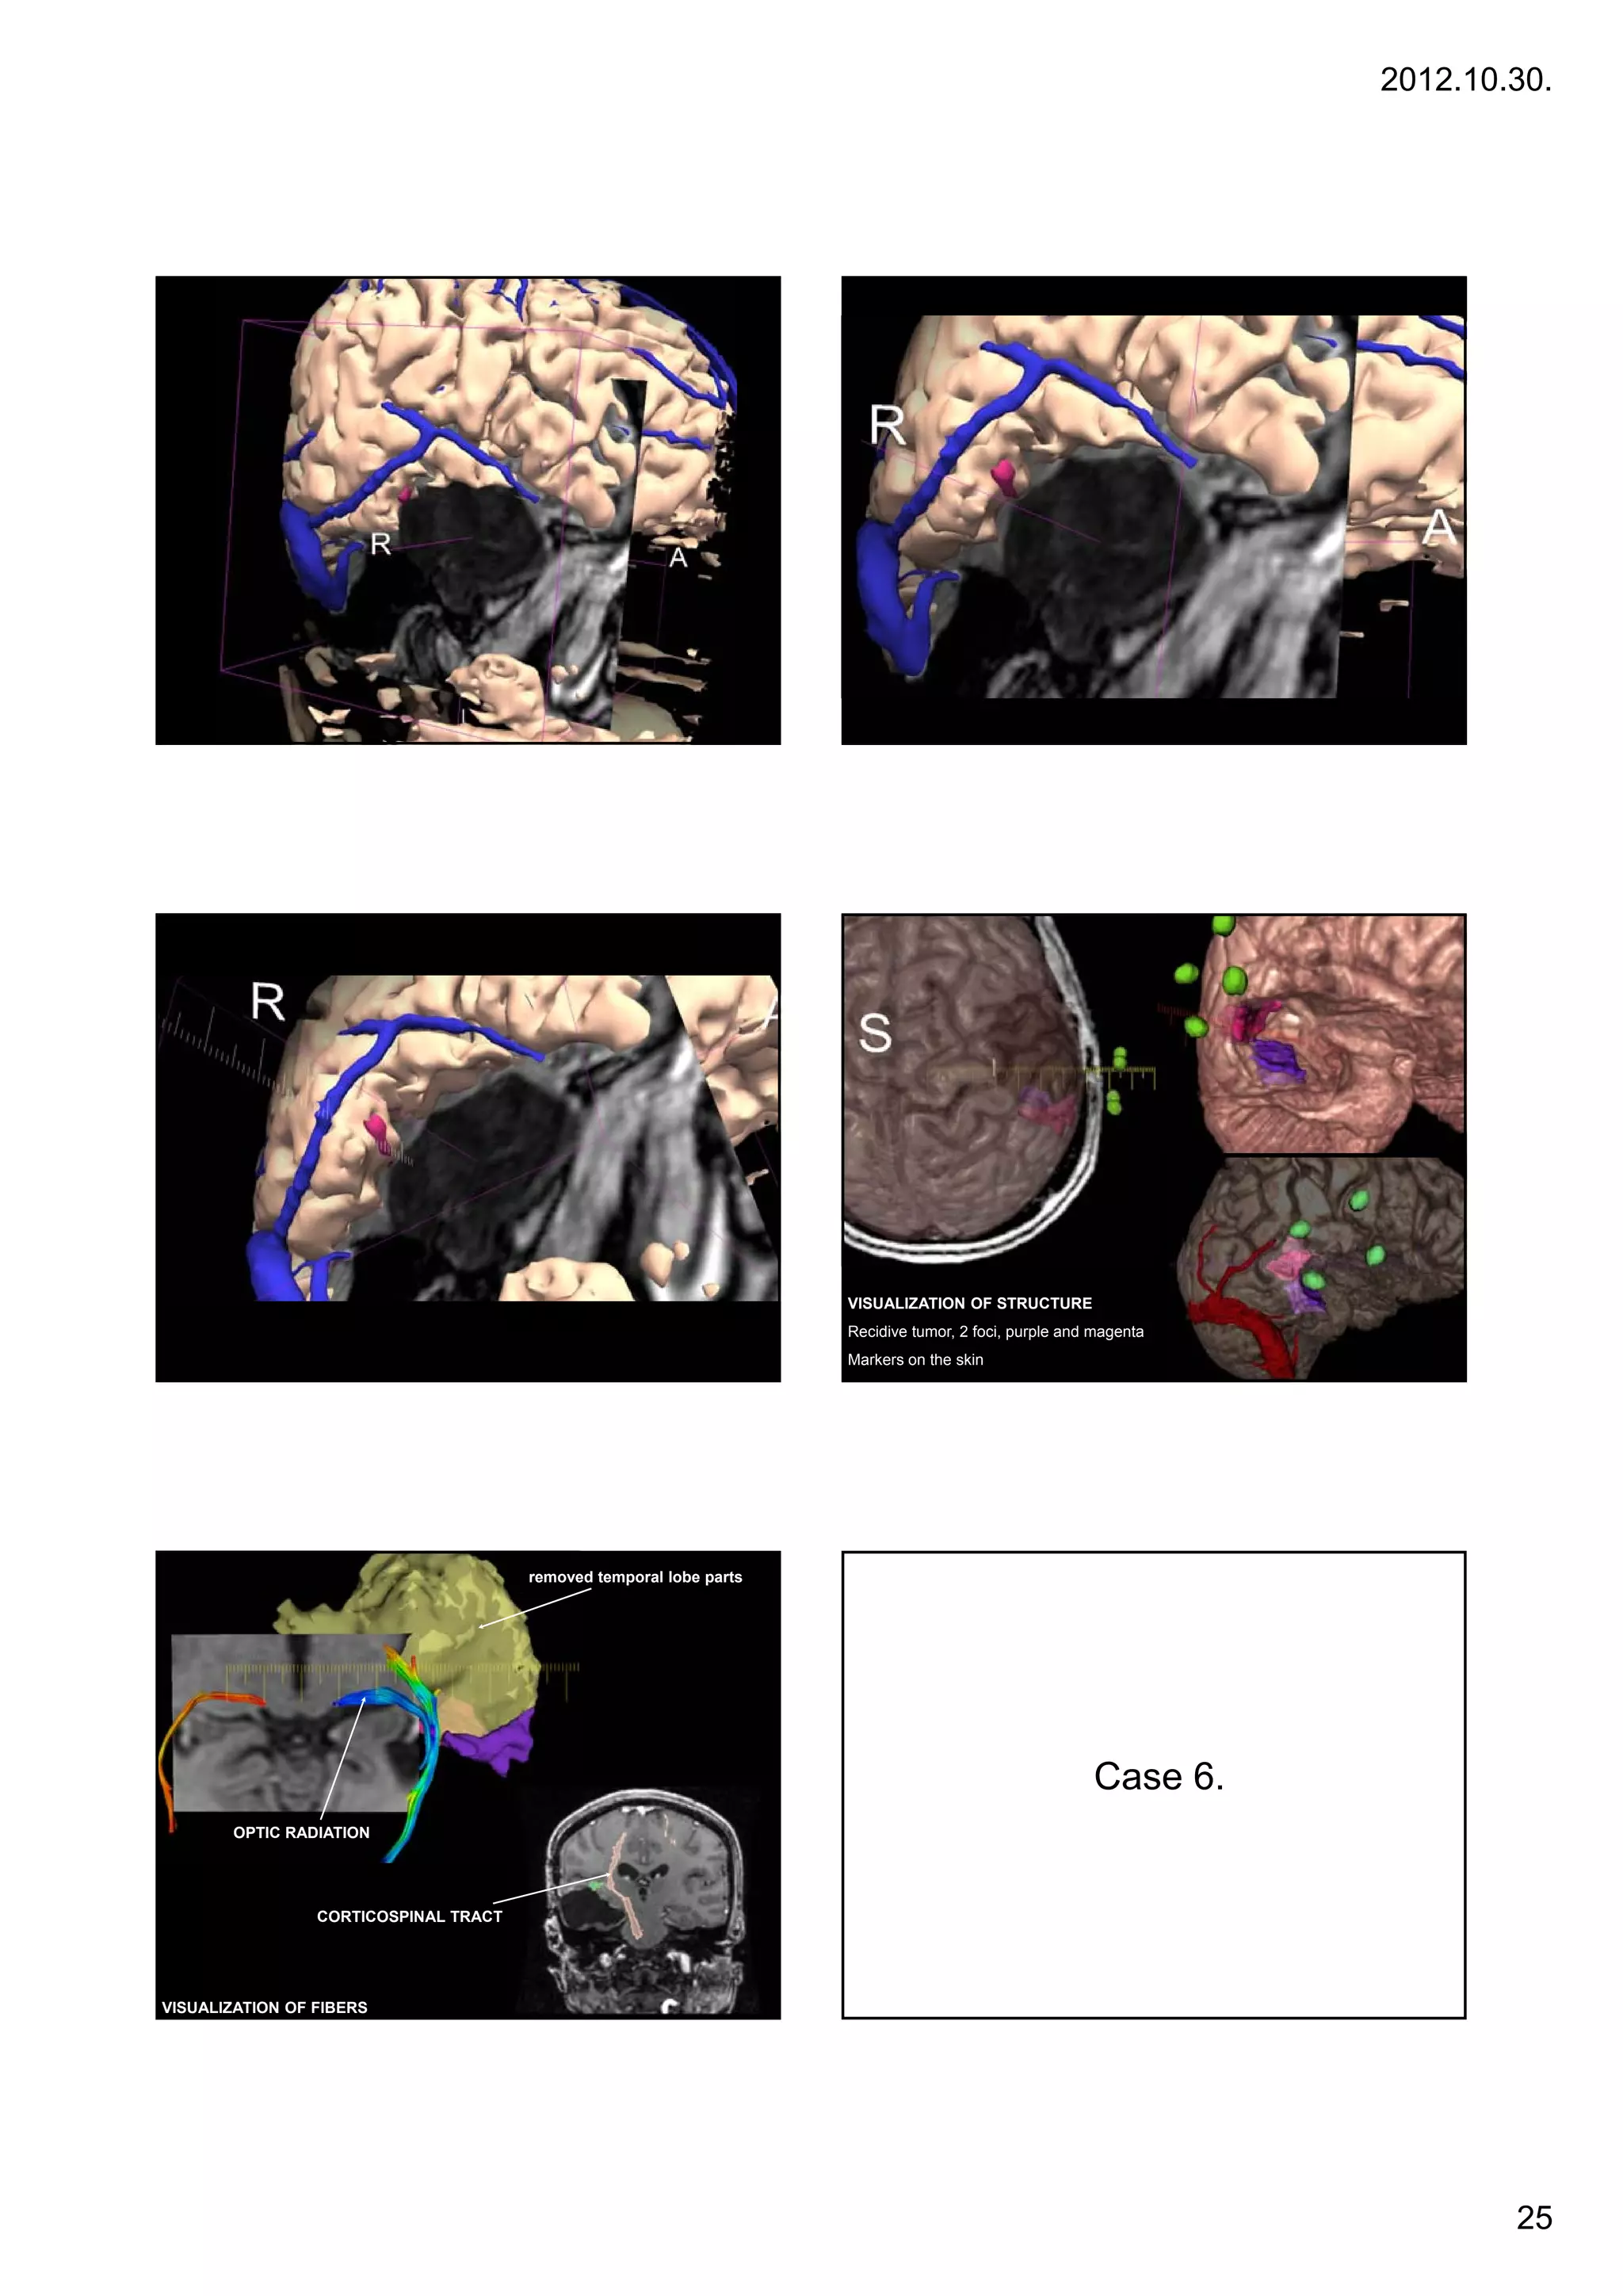

VISUALIZATION OF STRUCTURE

Recidive tumor, 2 foci, purple and magenta

Markers on the skin

removed temporal lobe parts

Case 6

6.

OPTIC RADIATION

CORTICOSPINAL TRACT

VISUALIZATION OF FIBERS